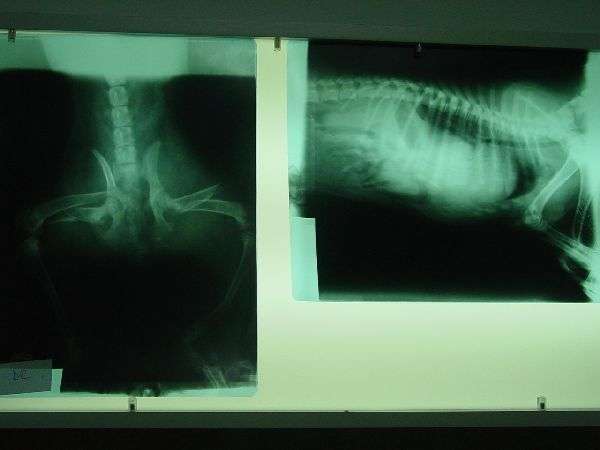

Aceasta catelusa a fost accidentata grav, fara noi nu mai avea nici o sansa de recuperare, acum se afla internata la clinica unde i s-au facut investigatii in urma carora s-au constat fracturi de picioare si ruptura de diafragma, vor fi costuri foarte mari dar asta nu ne va impiedica sa luptam pentru salvarea ei rugandu-va si pe voi prietenii animalelor si ai nostri sa fiti alaturi de noi cu orice credeti ca ar putea ajuta: publicitate, o mica donatie si orice credeti ca ar fi util pentru salvarea ei.